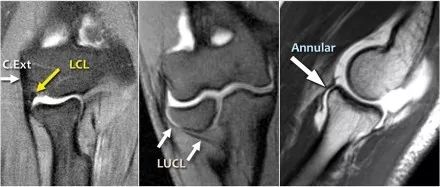

当您寻找桡侧副韧带时,首先要尝试识别常见的伸肌腱,因为在它下面你会发现桡侧副韧带(黄色箭头)。

当你向后走时,你会看到LUCL--侧面尺侧副韧带,它在桡骨头后面扫过(白色箭头)。环形韧带通常难以与RCL区分开,但有时可以在矢状MR-关节造影上识别。